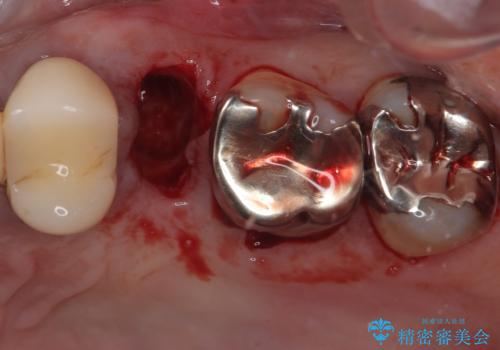

患者様の身体的・時間的負担を最小限に抑えるため、抜歯即時インプラントを選択しました。

この方法では、抜歯と同時にインプラントを埋入するため、

外科処置は1回のみ

抜歯と同日にインプラントを埋入し、さらに仮歯まで装着するため、治療当日から見た目と噛む機能の回復が可能です。治療期間中も審美性と日常生活の快適さを維持できます。